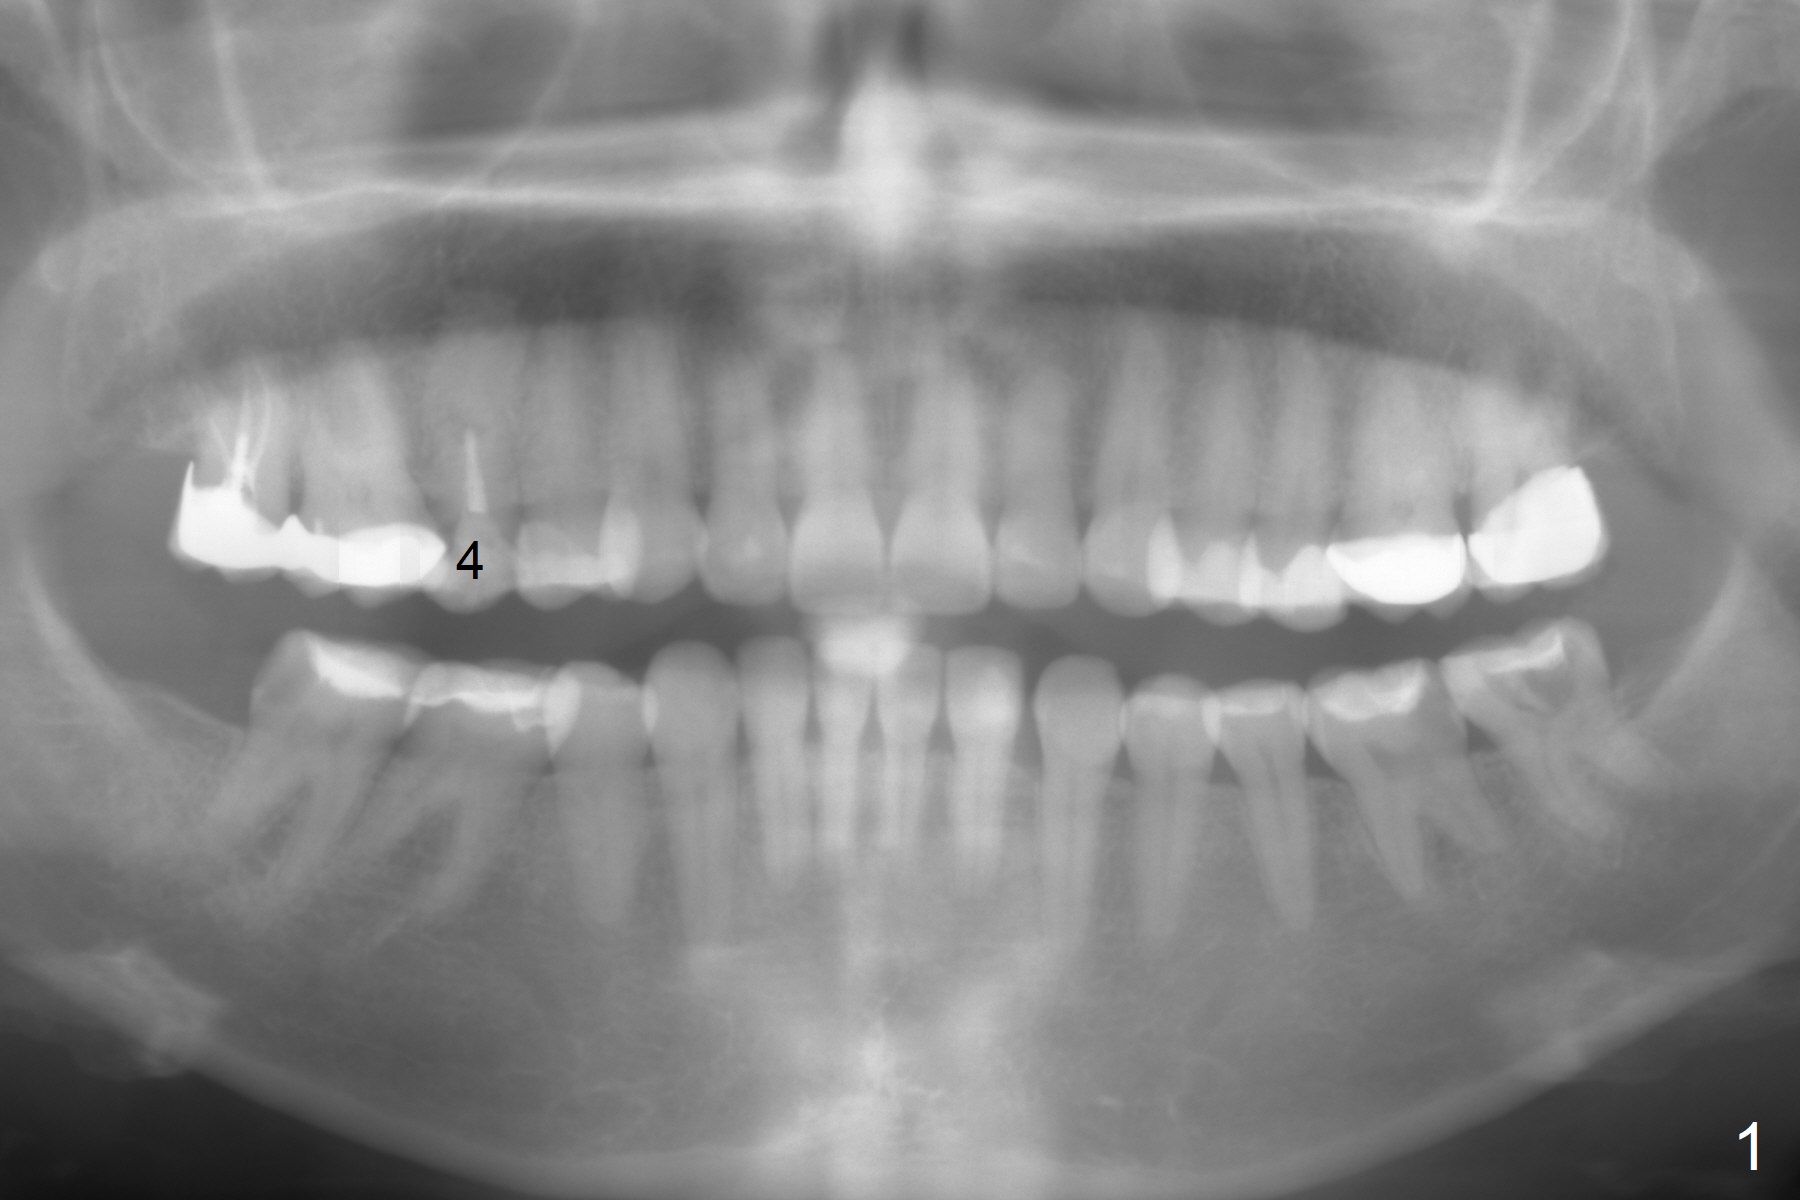

A 41-year-old woman has multiple restorations. One of them, the tooth #4, has palatally subgingival fracture. There is sufficient bone height (Fig.2,3). The apex seems to have ben resected with periapical radiopaque lesion (Fig.3 black *, possible synthetic or bovine bone). To get two point engagement into the native bone (red *), the longest bone-level implant will be placed.